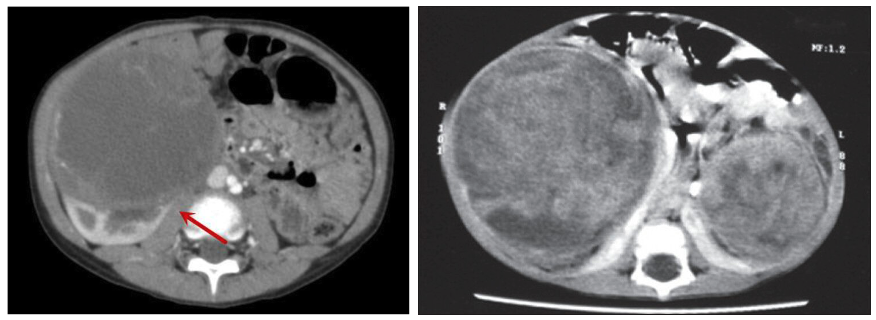

좌: wilm’s tumor in left kidney, enhancing renal tissue의 displacement (화살표)

abdominal vessel을 encase하지 않고 midline crossing을 보이지 않음.

우: bilateral wilms tumor

신경모세포종 vs 윌름 종양

• Neuroblastoma: midline crossing, major vessel encasement, calcification 동반

• nephroblastoma: midline 침범 x, vessel encasement x (밀어냄)